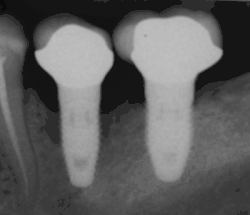

Clinically, peri-implantitis involves both inflammation of soft tissues and destruction of bone, therefore, there is usually evidence of both bone loss (assessed by a radiograph) and bleeding when nearby tissues are probed, a common finding for soft tissue inflammation. There have been reports of bone loss without any accompanying sign of soft tissue inflammation. Without evidence of bone loss, the diagnosis is restricted to peri-mucositis (see comparison between peri-implantitis and peri-implant mucositis below for more information).[2][3][4][5][7]

In healthy situation, there should be no sign of bone loss other than potential bone remodelling at the alveolar crest following implant placement.[2]

The shape of the alveolar bone in regions of bone loss varies depending on the buccal-lingual length (or cheek-to-tongue length) of the bone. Where this length is greater than the extent of the peri-implantitis, the region of bone loss can take the shape of a crater, with walls of bone surrounding the pathology;[4] this is the most common presentation of bone loss.[3] Where the buccal-lingual length is smaller, there may be no walls of bone surrounding the pathology.[4]

Peri-implant mucositis becomes peri-implantitis when bone resorption is identified around the implant on a radiograph as well as all the signs associated with peri-implant mucositis is seen. Often, pus may also exude from the tissues surrounding the implant. However, mobility of the implant is not a sign of peri-implantitis as this disease begins at the margins of the implant. Only in the most severe cases of peri-implantitis, implant mobility may be observed where minimal bone tissue remains.